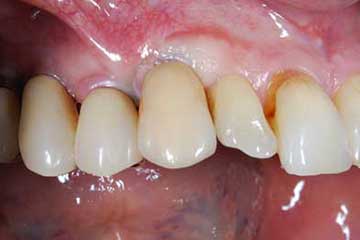

Lembo libero per correggere una recessione gengivale